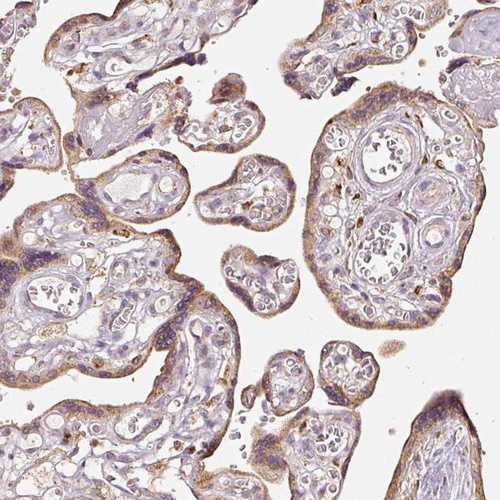

Immunohistochemistry analysis in human placenta and skeletal muscle tissues using HPA029041 antibody. Corresponding MTHFD1L RNA-seq data are presented for the same tissues.